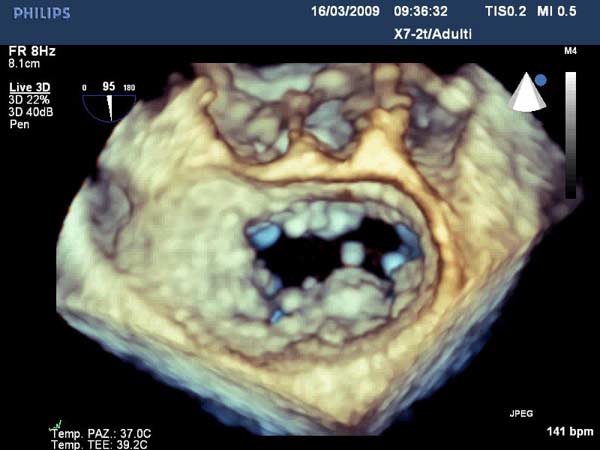

Figure 7

In absence of controlled clinical trial data which are forthcoming from the EVEREST II randomized study, the indications for the MitraClip therapy are currently based on registry experience and will evolve as the technique improves, experience is growing and the data to demonstrate efficacy and safety becomes available. At this time, the best indication for the MitraClip therapy is for symptomatic patients with clinically significant functional or degenerative MR who are at high or increased risk for open heart surgery. From a pure technical standpoint, the procedure so far has only been demonstrated in a subgroup of patients with specific anatomical characteristics which are summarized below and shown in Figure 3. Anatomic suitability is assessed by transesophageal echocardiography, and mitral regurgitation should originate from the central portion of the valve involving the A2-P2 segments, since the device is not ideal to work in the commissures at this time; the mechanism of MR can be either a prolapse/flail or MR due to restricted leaflet motion unrelated to rheumatic disease; the separation between the two leaflets at the site of regurgitation should be limited; severe annular dilatation and/or severe calcification should be absent or is relevant. In case of flail, the flail segment width should be less than 15 mm, and the flail gap less than 10 mm. Figure 4 is a 3D echo image of a patient with posterior leaflet prolapse selected for MitraClip therapy. In case of functional MR, the leaflets should have a minimal residual tissue available for coaptation with the MitraClip device. Figure 5 shows 2D color Doppler jet extension over the coaptation line at TEE short axis transgastric view, while Figure 6 shows the tenting area and the coaptation depth of a patient undergoing MitraClip implant.